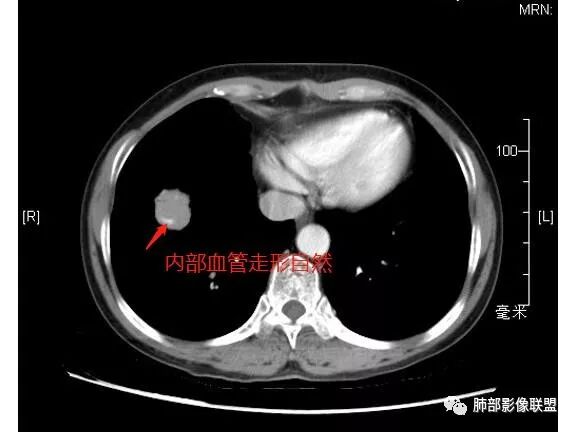

内部支气管扩张,穿行血管形态自然,支持malt。

轻度分叶,支气管穿行,轻中度强化,血管漂浮,考虑MALT

病灶呈圆形,轻度分叶,内见血管及支气管影,考虑MALT。

右肺下叶前基底段结节 边缘磨玻璃密度较清 内部支气管扩张,轻中度强化 穿行血管形态自然,支持淋巴瘤。

晨读,右肺下叶前基底段实性结节,边缘膨隆,可见多发浅分叶,结节内密度均匀,增强后呈轻度均匀强化,血管穿行走形自然,首先考虑恶性肿瘤,内有支气管穿行,淋巴瘤可能大,腺癌待排。

内部支气管走形非常自然,达远端稍扩张;内部血管穿行也非常自然

恶性的血管穿行自然,包括支气管稍扩张,最常见还是淋巴瘤,它强化比较均匀;

血管造影征:肿瘤组织浸润引起间质增厚、肺泡壁破坏、肺泡腔充填,而周围充盈血管走行自然,未受肿瘤侵犯。